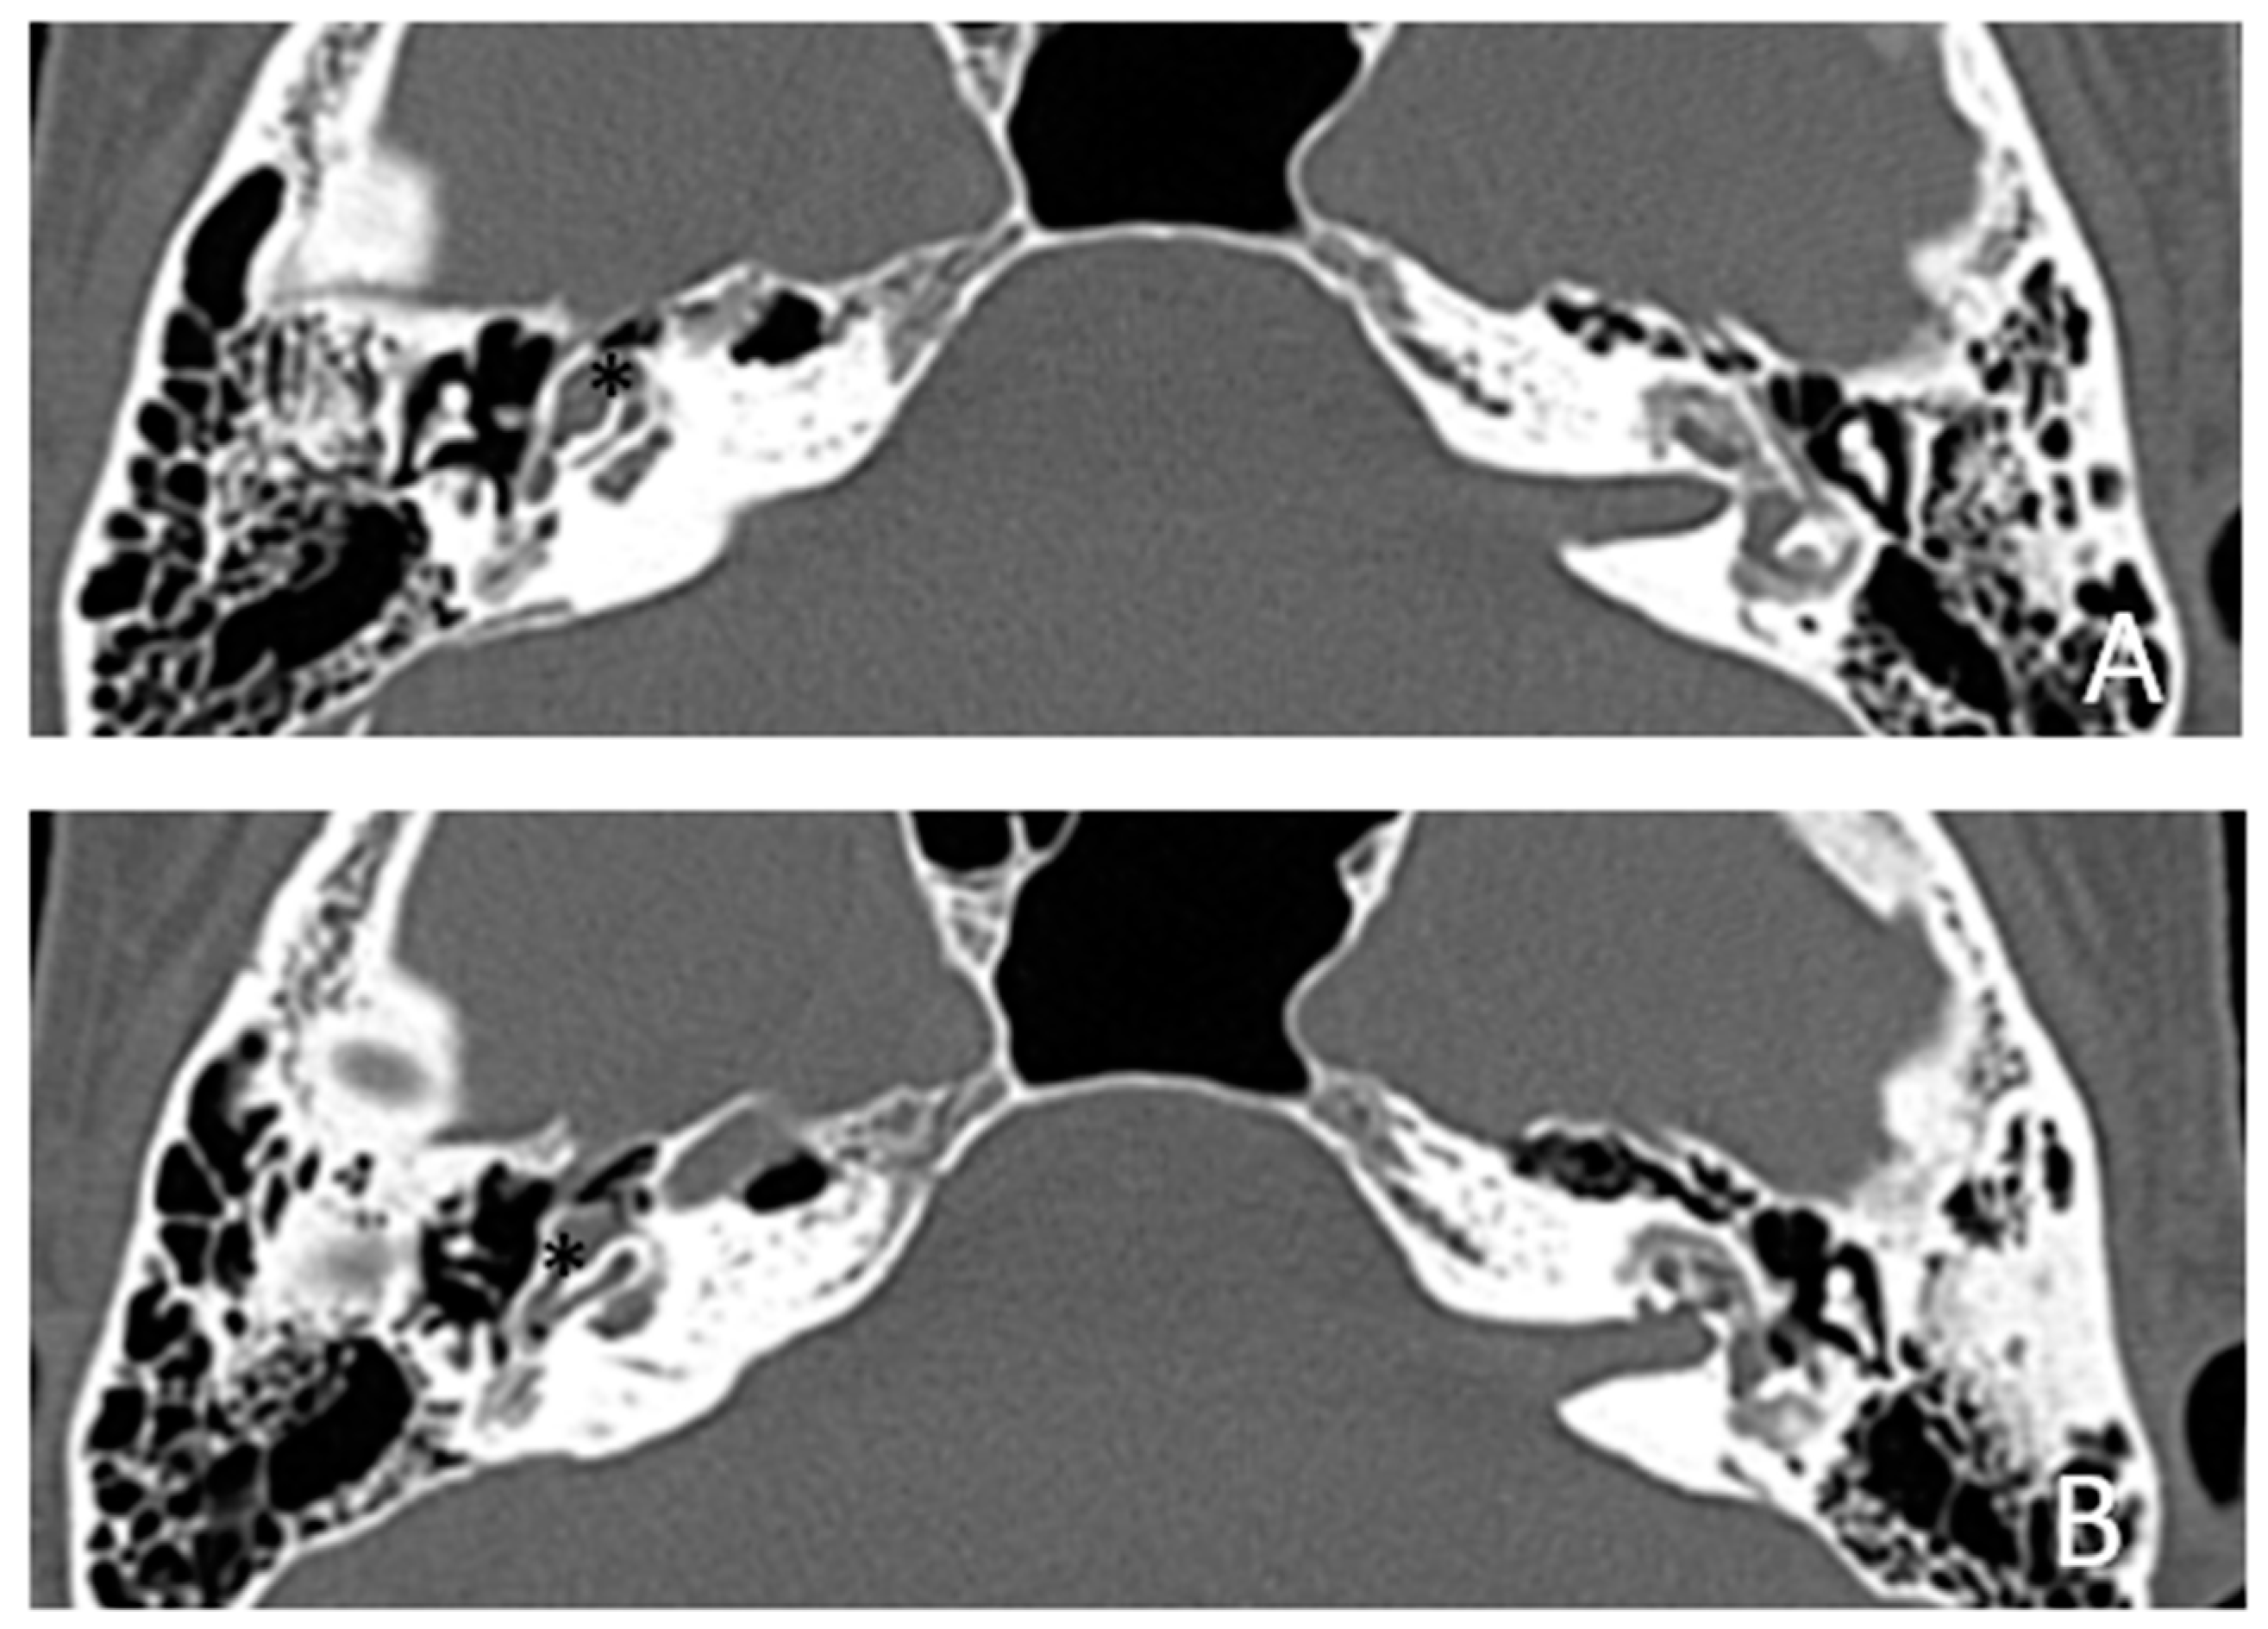

Figure 7. CT images of patient #4 with otosclerosis. A and B, axial plane. The cavity around the cochlea is clearly visible as well as the communication of the cavitating osteorarefation with the cochlea,marked with asterisks.